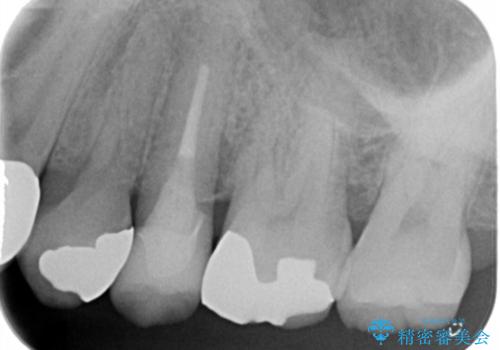

- 銀の詰め物をやりかえたい。とのことで来院。

白い物を希望されたので、以下の提案を行い選んで頂いた。

①セラミックインレーにやりかえ

噛む面は白くなり、歯質を多く削らなくてすむが、

表面の黒いところまでは覆えない。

②ジルコニアクラウンで被せる

表面の黒いところまで覆う事ができる。

ただし、①よりも歯を大きく削ることになる。

患者様と相談し、黒いところも目立たなくしたいとのご希望だった。

そのため、歯質の削除量は増えるが、クラウンで被せる②の方針で行うことになった。

歯の表面の黒いところは虫歯ではなく

歯ブラシによる摩耗か歯ぎしりによるくさび状欠損によるものです。

そのままだと水などが染みてくる原因にもなります。